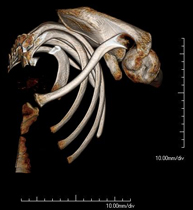

- TC Clavículas Exploración radiológica que mediante un sistema de rayos X y detectores que giran alrededor del paciente, reconstruyendo las imágenes por ordenador, permite el estudio detallado de las clavículas. Exploración radiológica que mediante un sistema de rayos X y detectores que giran alrededor del paciente, reconstruyendo las imágenes por ordenador, permite el estudio detallado de las clavículas.

- TC Parrilla costal Exploración radiológica que mediante un sistema de rayos X y detectores que giran alrededor del paciente, reconstruyendo las imágenes por ordenador, permite el estudio detallado de la parrilla costal. Exploración radiológica que mediante un sistema de rayos X y detectores que giran alrededor del paciente, reconstruyendo las imágenes por ordenador, permite el estudio detallado de la parrilla costal.